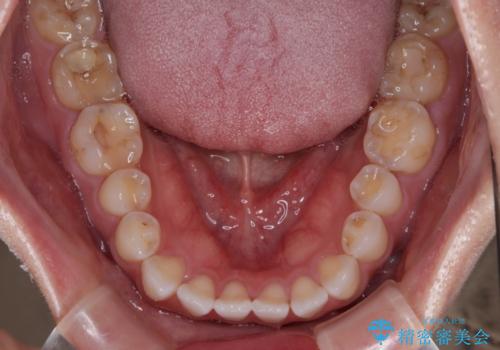

捻れた前歯を楽して改善 ワイヤー装置での非抜歯矯正

- 上下前歯のデコボコを気にして来院された患者様です。

ワイヤー矯正でもマウスピース矯正でも可能でしたが、短期間で、自身の手を煩わせることなく治療を行いたいとのことで、ワイヤー装置にて矯正治療を行うこととしました。

ご本人の中では2年近くかかるものと思っていたそうですが、1年で治療を終えることができ、大変満足していらっしゃいました。